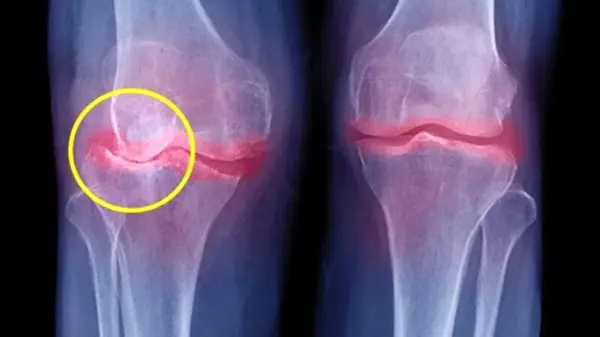

کرونا ویروس می تواند مفاصل اشخاص را هم درگیر کند.

علی آزاد اظهار داشت: چاقی و افزایش وزن با فشار بر مفاصل سبب ساییدگی مفصل، ورم مفاصل و استخوان‌ها می شود که این افزایش وزن و چاقی در دوران پاندمی کرونا به دلیل قرنطینه خانگی و خانه نشینی و ... شدت یافته است.

جراح و متخصص استخوان اضافه کرد: چاقی سرعت تخریب مفاصل را افزایش می دهد و گاه سبب عارضه‌های مزمن و ماندگار می‌شود بنابراین کاهش وزن یکی از مهمترین دستورات پزشکی به مبتلایان به آرتروز(ساییدگی مفصل) است که فشار بر مفاصل را کاهش می دهد و مانع از ساییدگی مفاصل می‌شود.

جراح و متخصص استخوان اضافه کرد: این ساییدگی با افزایش سن تشدید می‌ یابد و می‌تواند منشاء بروز خوردگی استخوان نیز باشد و در صورت تداوم خاصیت اولیه مفصل را هم از بین می برد.